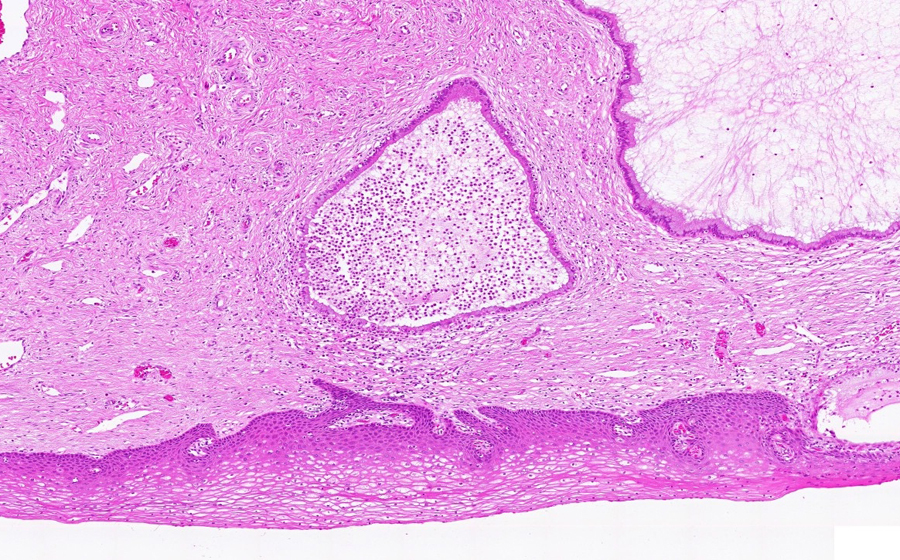

Image 3 - 100X

Slide 3 - Image 3